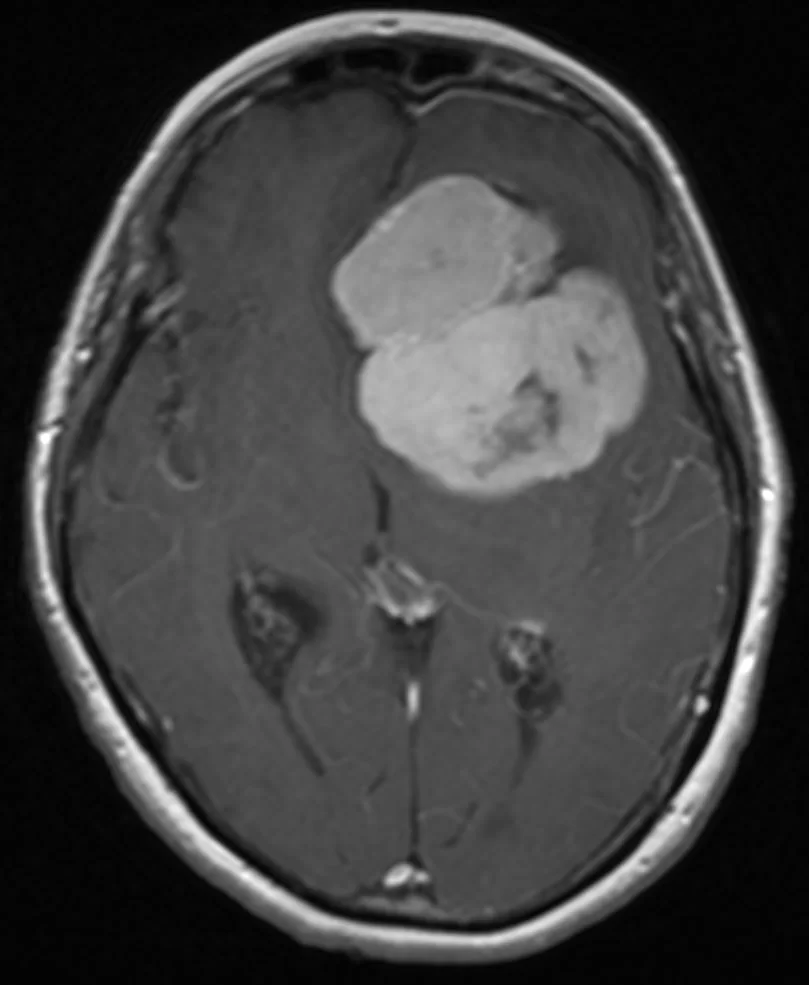

Ο απεικονιστικός έλεγχος με μαγνητική τομογραφία ανέδειξε ευμεγέθη όγκο της πτέρυγας του σφηνοειδούς αριστερά, συμβατό με μηνιγγίωμα.

Πρόκειται για ένα ιδιαίτερα μεγάλο μηνιγγίωμα, στην επικρατούσα πλευρά (αριστερά), το οποίο πίεζε δομές όπως τα οπτικά νεύρα και είχε «ενσωματώσει» σημαντικά αγγεία του εγκεφάλου (αριστερή καρωτίδα και κλάδους της). Όγκοι σαν και αυτόν χρειάζονται υπομονή και καλή μικροχειρουργική τεχνική προκειμένω να παρασκευαστούν και να προφυλαχθούν όλα τα κρίσιμα αγγεία. Η υποχώρηση των συμπτωμάτων ήταν άμεση.